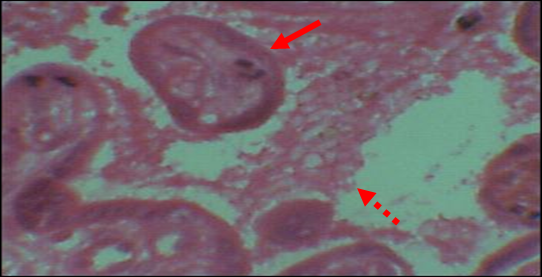

Overall (HIV+ and HIV-), 27.99% (82/293) of placentas showed no trace of malaria infection (Cat N). Category 1 lesions (Cat 1) were found in 19.45% (57/293) of placentas. Those of category 2 (Cat 2) were found in 29.01% (85/293) and lesions of category 3 (Cat 3) concerned 23.55% (69/293) of placentas. The lesions most frequently found in HIV+ mothers were those of Cat 2, 71/145, or 49.00% compared to 14/148, or 9.50% for HIV- mothers (OR=26.92; CI at 95%=11.10-67.60; p<0.0001). While Cat 3 lesions were more prevalent in HIV- mothers 46/148 (31.10%) vs 23/145 (15.80%), found in HIV+ mothers (OR=2.65; CI to 95%=1.15-6.21; p=0.020; (Table 4, Figures 1, 2, 3).

Figure 3 Microscopic picture of category 3 showing clumps of malarial pigment (hemozoin) in the villous stroma (solid arrow) and empty RBC EIVs (dotted arrow) HE : x100.